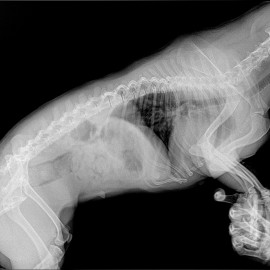

Наш пациент собака Маня 4 года.

Обратились с жалобами на боли. Собака ходила с опущенной головой, боли при поднятии головы вверх, боли при движении.

Собаке был поставлен диагноз: экструзия диска на уровне С3-С4, протрузия диска С6-С7.

Снимок 1 до операции.